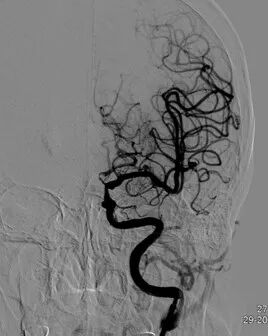

◆ 右侧颈内动脉以及右侧大脑中、前动脉显影良好,对左侧大脑中动脉部分代偿供血。

导丝怎么扩重磅!NOVA颅内药物球扩支架湖北首例植入!_https://www.jmylbn.com_新闻资讯_第6张

右侧颈内动脉造影

◆ 椎动脉、基底动脉脊大脑后动脉等各分支显影良好。

导丝怎么扩重磅!NOVA颅内药物球扩支架湖北首例植入!_https://www.jmylbn.com_新闻资讯_第7张

椎动脉造影